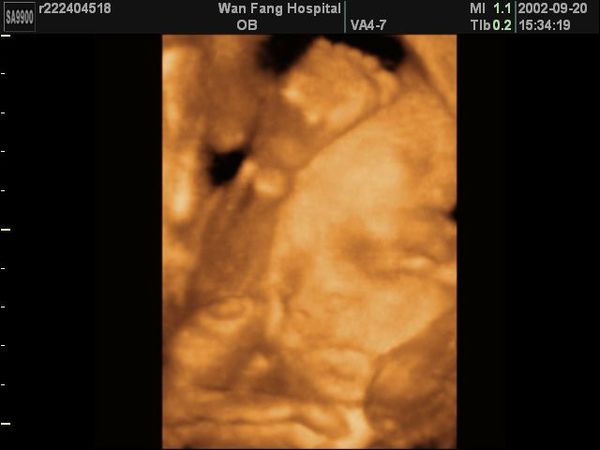

早上6點多,產兆出現了,第3胎,我以為小BABY會很快就出來和我見面,沒想到早上9點多到台大產房一檢查,根本沒開,但是有規則3到5分鐘一次的陣痛,不是超痛,被護士趕回去,下午睡一下午覺,居然不痛了....晚上8、9點才又開始規則陣痛,但也較痛一些, 想一想還是再去一趟台大吧!晚上9點多還先帶新來的菲傭去萬芳醫院打國際電話,10點多一到台大醫院還是沒開,天啊!越來越痛了,居然都沒進展,雖然是第3胎,心中仍不由得開始害怕,不知會痛多久,半夜12點多醫生一照超音波說--[胎兒頭的位置不對,較難開] [可能會等很久] ,但是因為是第3胎,醫生也不敢叫我們回家睡覺,我心想"越來越痛了,BABY要孝順一點喔!,不要讓馬麻痛太久,好不好".....後來我和把拔決定既然可能會耗很久,不如租個VIP單人待產室來享受一下 ,反正這輩子也沒住過醫院的VIP病房,原本還期待會不會像五星級飯店的高級設施,很遺憾!只是比普通待產室,人少一些,放了兩張床 ,一張產婦的,一張陪產者的.....結果沒想到才剛躺上床上,把拔才去辦住院,胎兒監控器一裝, 哇咧 ! 痛死了 !臭把拔去了好久,居然還買泡麵回來吃, 后~他以為他在野餐喔!!我開始語無倫次叫著--[把拔,好痛喔!怎麼辦!] ......就這樣一直痛到凌晨4點,護士來檢查, 開了,可以進產房了, 哇ㄚ!我好高興ㄛ(心中高興,表情還是很痛苦滴!)終於快解脫了,沒想到進了產房,真正的不安全感才出現, 因為醫生還沒來,產房裡一堆小醫生小護士,把我架上產台,更糟糕的是他們不疾不徐,還邊交談著-- [我看華醫師是來不及了,第3胎耶!] [先量血壓] 我好像一隻待宰的羊,驚慌的被綁在屠殺台上,又不知何時可以解脫,旁邊的屠夫,還可以邊聊天邊擦拭屠刀, 我急著問--[華醫師來了沒有?]..........[我可以用力嗎?]..........[不會裂傷嗎?] 終於有一個男助產士有回應--[沒關係,可以用力了?我們還有別的醫生在] [來!用力] [重來][再一次]